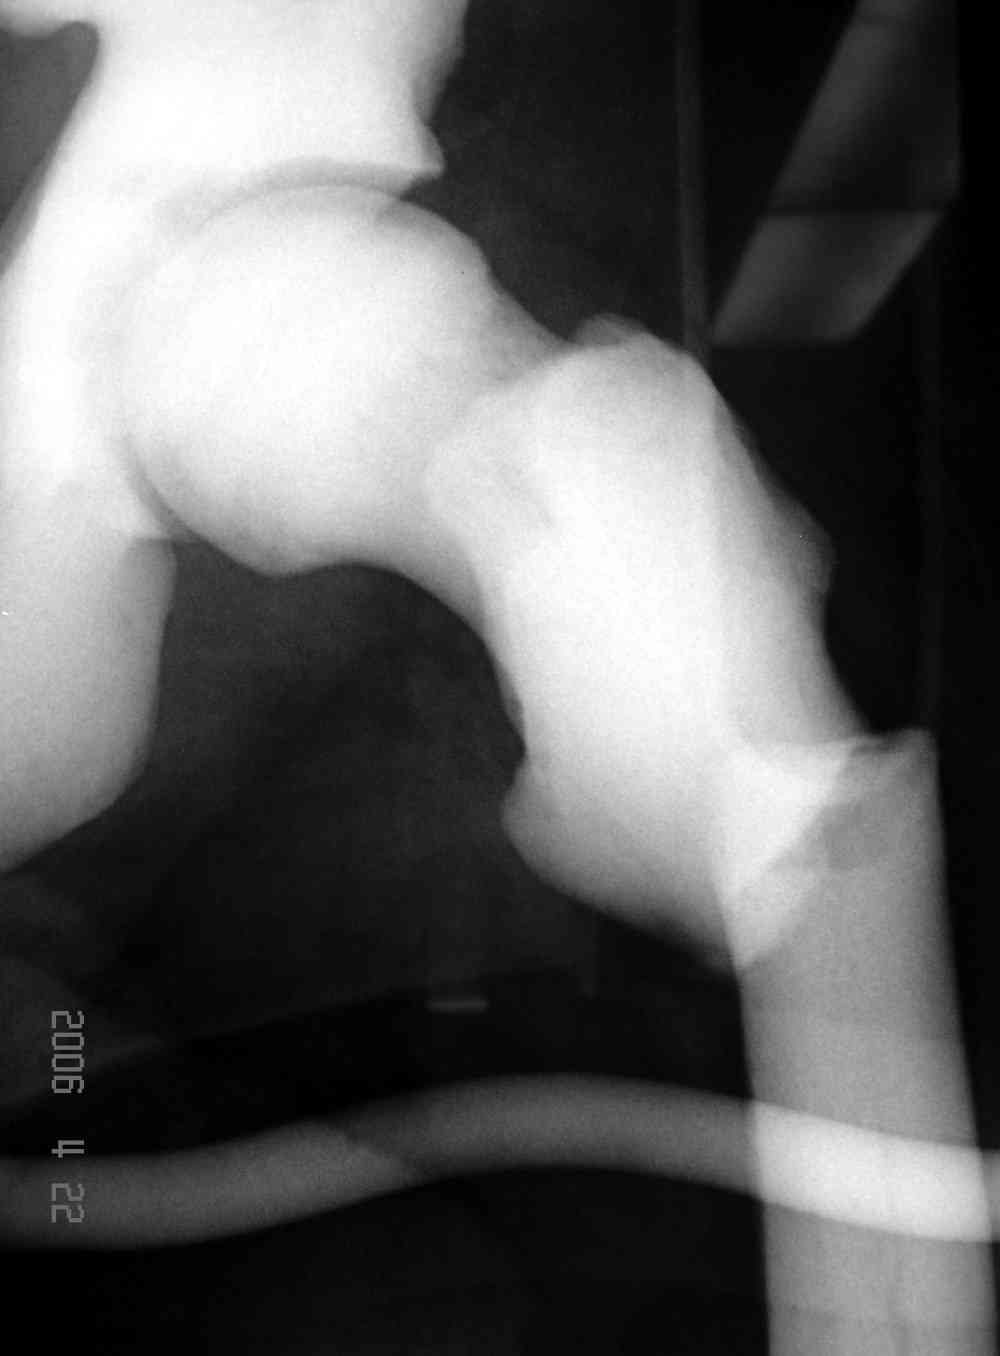

После неудачной попытки скелетного вытяжения в первом мед.учреждении, после осмотра снимков и изучения истории, поставили диагноз “Остеопетроз” или мраморная болезнь, редкая наследственная костная паталогия, где имеется нарушение формации остеокластов.

Диагноз клинико-рентгенологический: характерная рентгенологическая картина, частые патологические переломы... Заболевание наследственное, в наших краях редкое, передается рецессивным геном и прявляется в гомозиготном организме, поэтому важна информация о бабушках, прадедушках, пра-пра....

А как проверить, "если только это мраморная болезнь"? Какие анализы нужны, чтобы подтвердить предполагаемый диагноз?

Не вызывает ли подозрение, что отсутствует медуллярный канал, как просверлить канал?